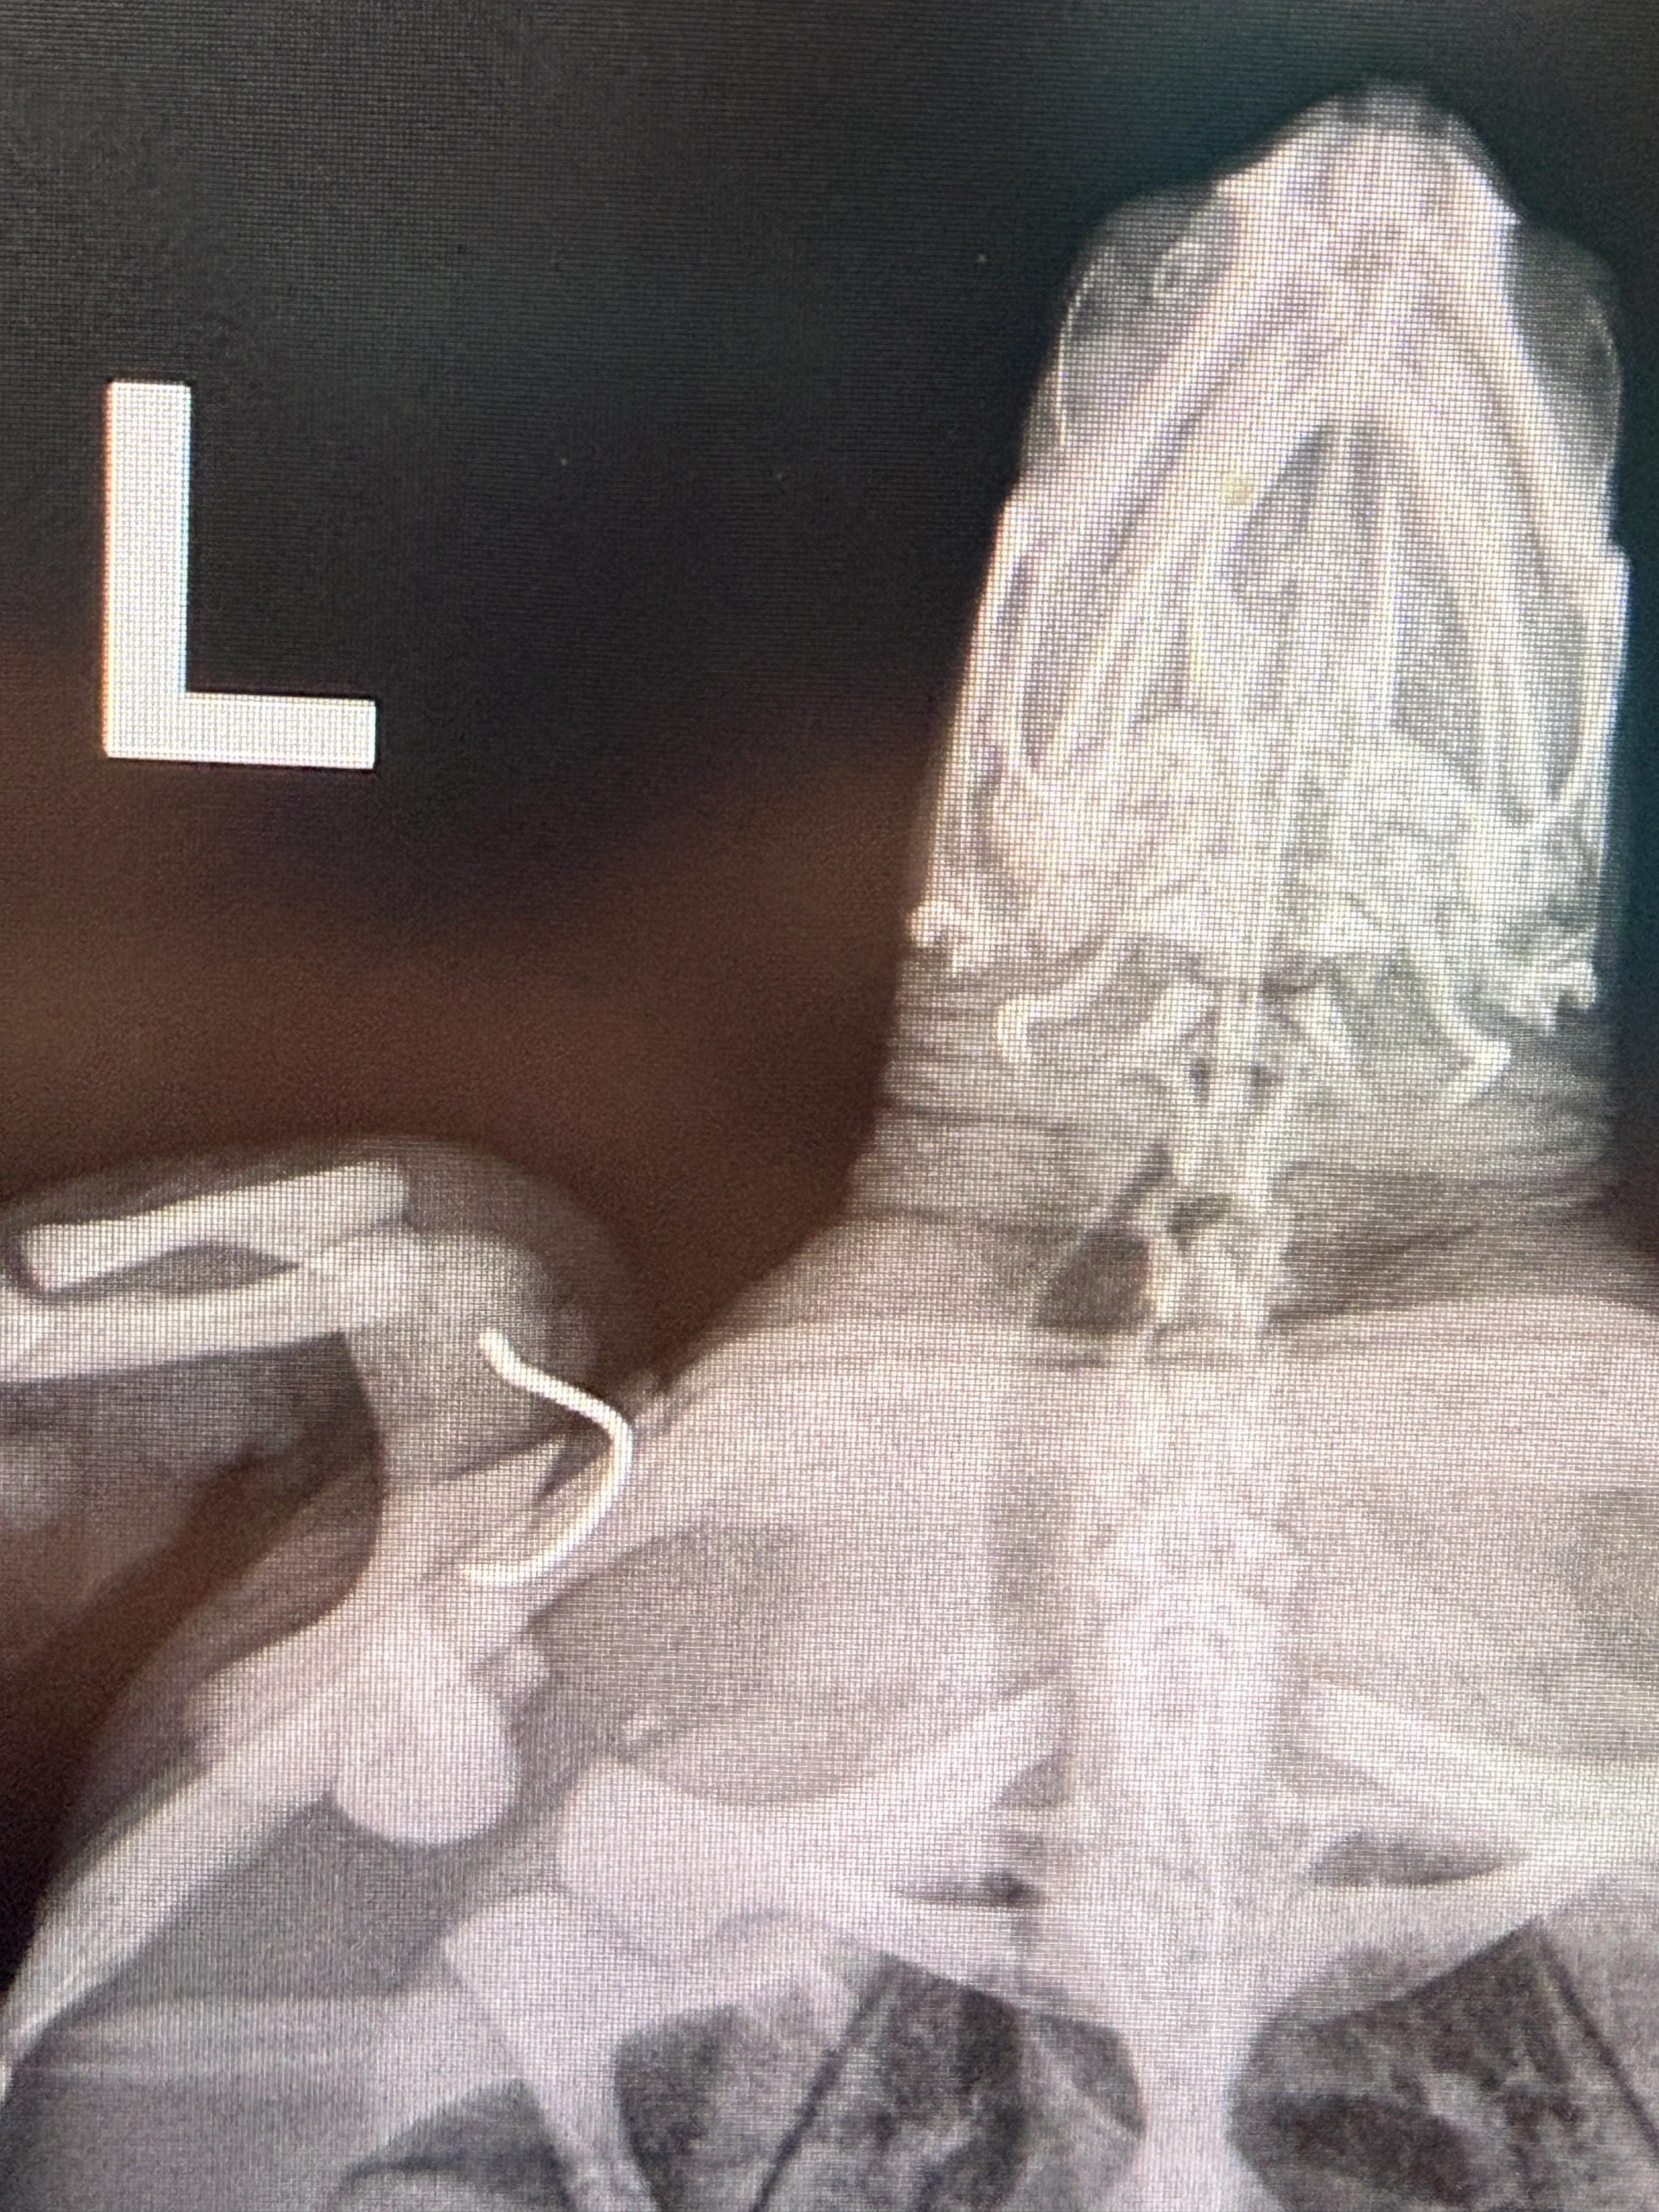

External Wounds: Hook in left shoulder